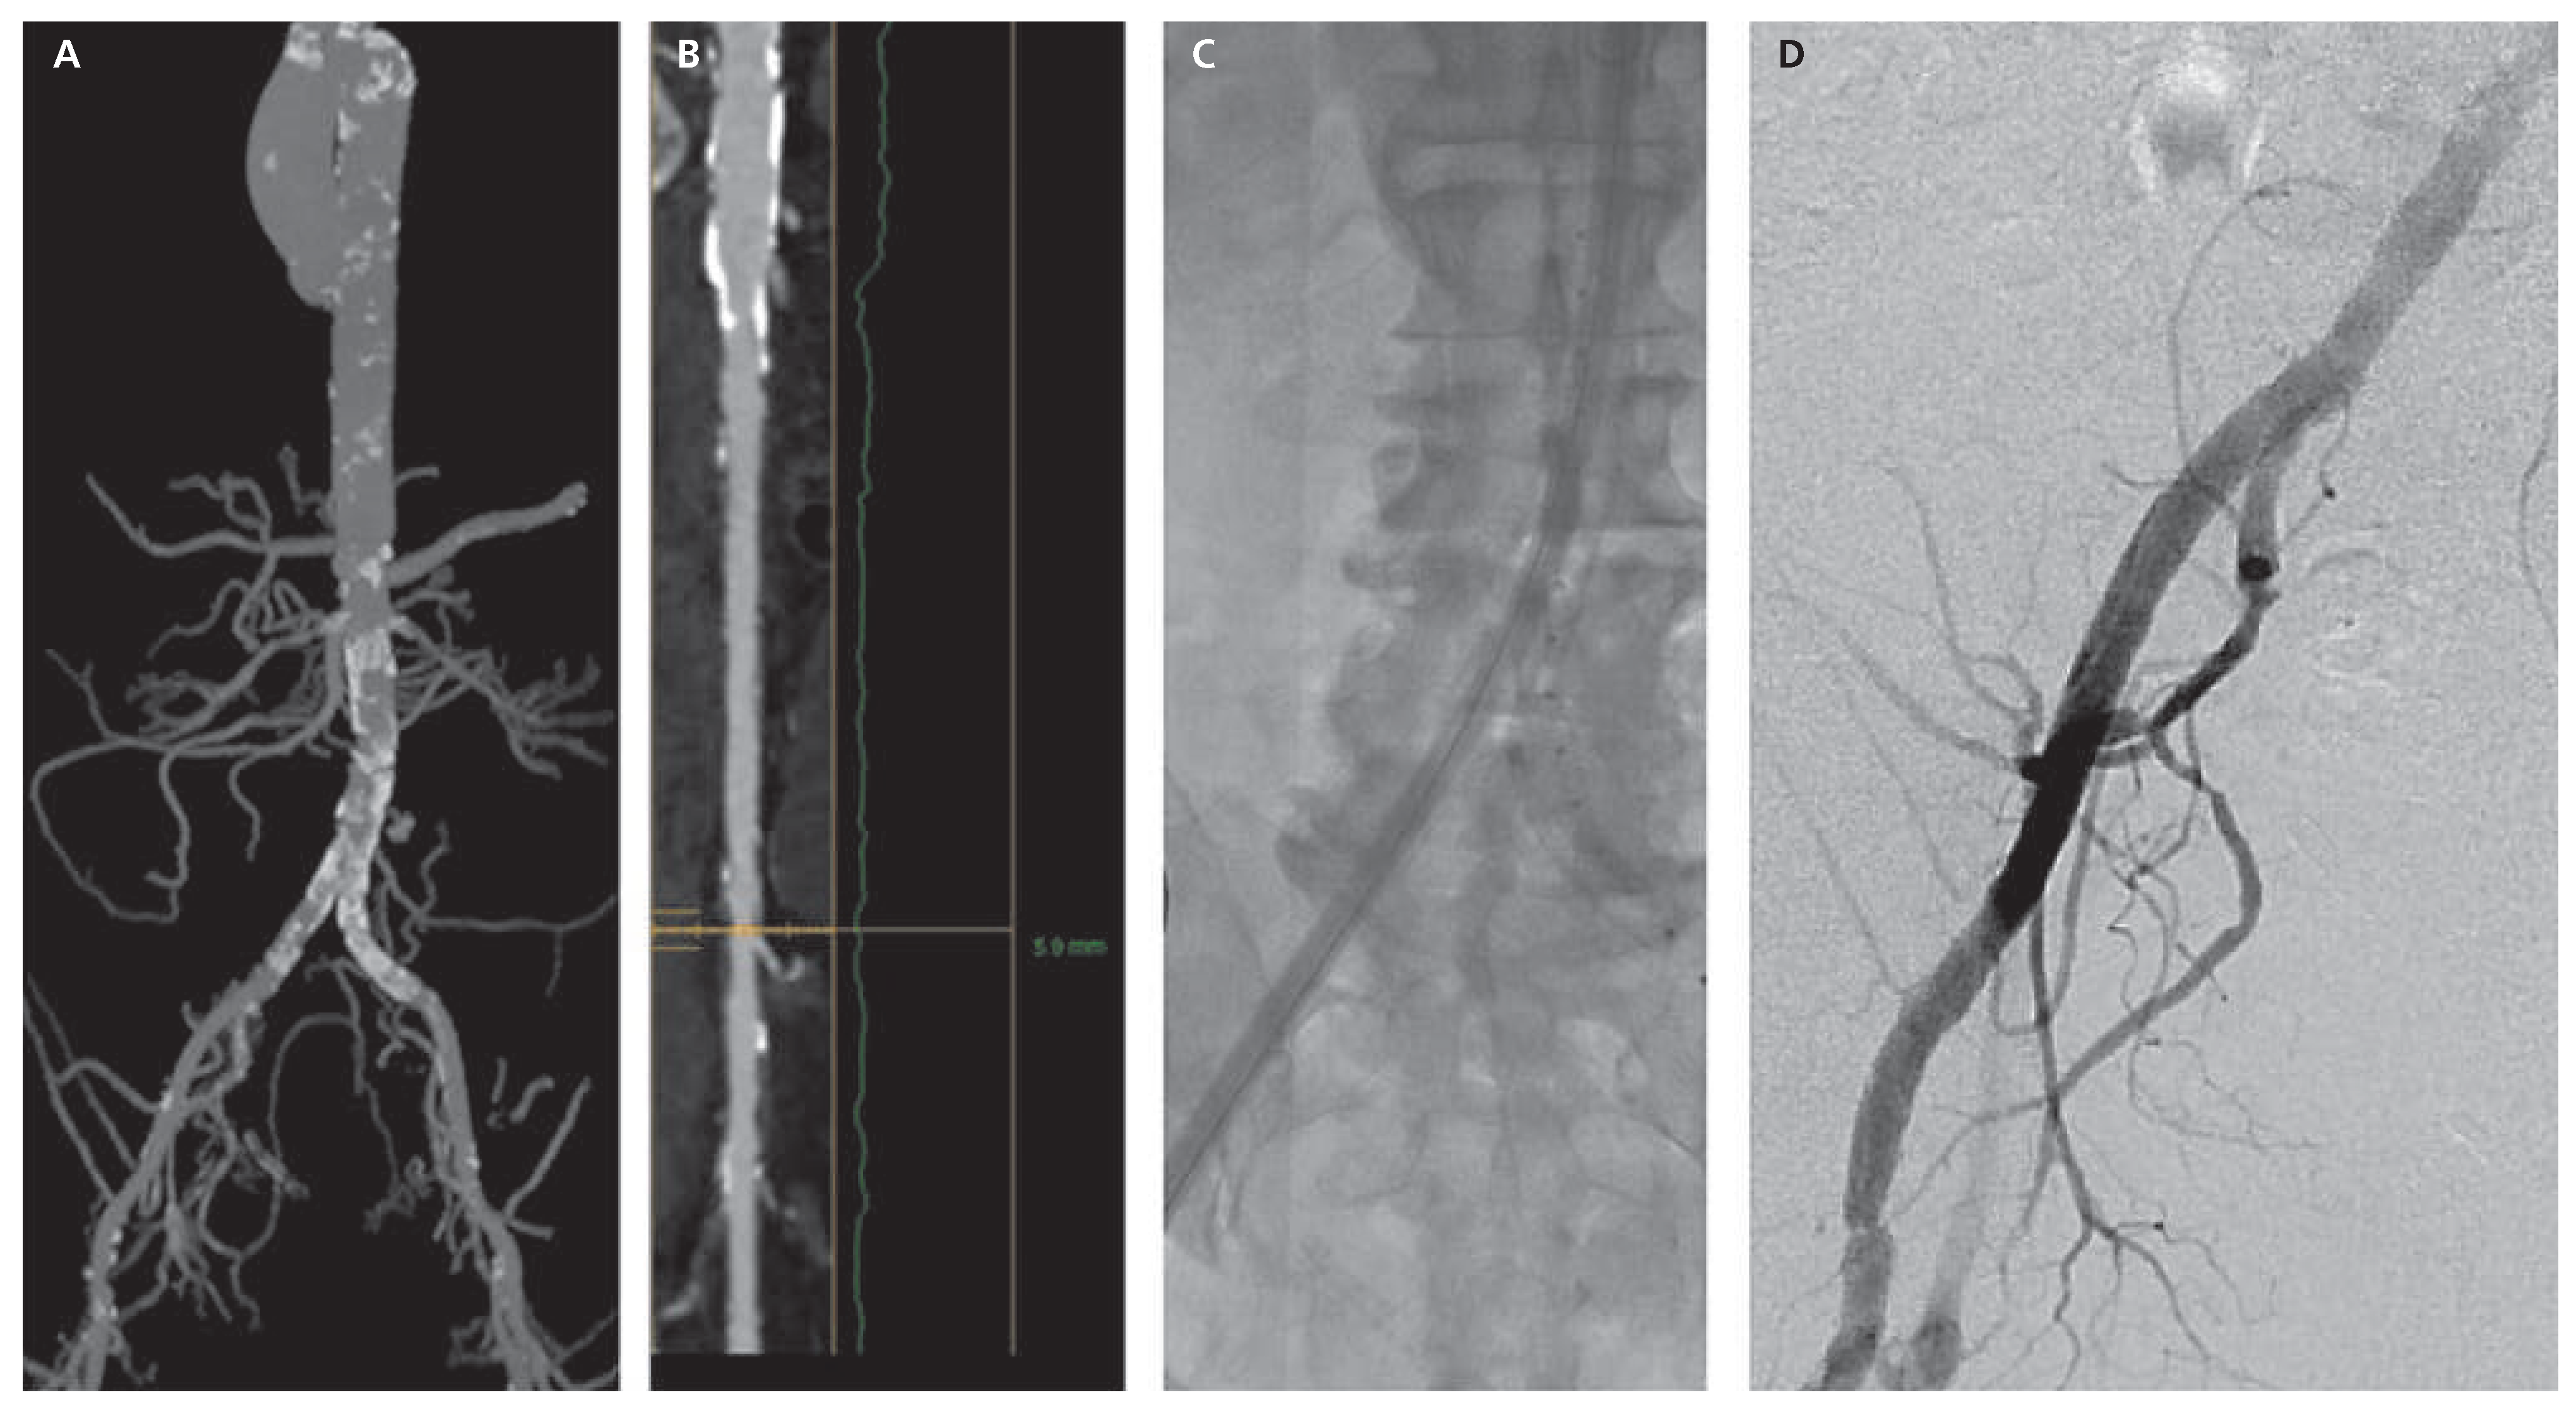

Figure 6. Successful case of SoloPath® use in a borderline anatomy (patient 9). A CT scan assessment using MIP (Maximum Intensity Projection) showing the bilateral ilio-femoral axis with calcification at the level of the common iliac arteries. B Reconstruction of the right ilio-femoral axis with the smallest diameter measured at 5.9 mm. C SoloPath® 19-F sheath inflated. D Final angiographic control.

In our experience of 10 cases (Table 1, Figure 6), we were confronted with two CoreValve® embolisations with successful extraction of the valve through the SoloPath® sheath. The distal tip of the sheath was strong enough to allow recapture. One additional downside of the technology is that the haemostatic valve leaks once a stiff wire is in place. We obviate this limitation by inserting a 9-F sheath into the SoloPath® during the procedure phase of native valve crossing and baseline hemodynamic assessment. Finally, when advancing the folded sheath, it should be deeply advanced quite rapidly to avoid significant blood leakage through the folded portion and its W-shaped channel.